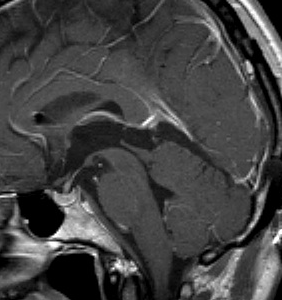

これも偶然発見された無症状の女性の小さい松果体細胞腫ですが,ほとんど実質性でのう胞がありません。右はCISSという画像です。中脳の視蓋は圧迫されて変形していますが,中脳水道がまだ閉塞していないのがよくわかります。

左側はMRI血管像です。赤く塗った松果体腫瘍がたくさんの血管とくに静脈に囲まれていて深い位置にあるのがわかります。右は手術後のMRIです。幸い後交連というところも残せたので眼球運動障害(ものが2重に見える)という後遺症は出ませんでした。